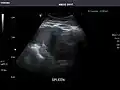

Spleen: Normal in size.

Spleen -